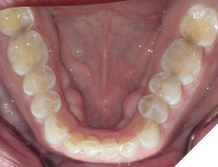

The majority of the orthodontic practices offer a period of “supervised retention” to their patients and communicates the customized retention recommendation with the patient’s general dentists. It is extremely important to work as a team to achieve long term clinical success in maintaining a functional bite and aesthetic smile. The general dentists continue to see their patients on a regular basis and have an opportunity to assess the orthodontic retainers and the bite after the supervised retention period is completed by the orthodontists. With great care, orthodontic retainers would serve for a long time (Fig. 1) without any major issues. However, in some cases, the failure to notice the clinical problems early on results in functional issues that would require a comprehensive orthodontic treatment to correct it (Fig. 2).

Fig. 1A

Fig. 1B

Fig. 1C